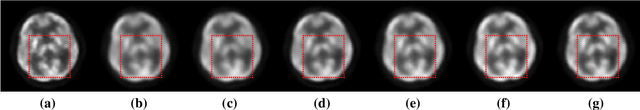

Abstract:Neurite Orientation Dispersion and Density Imaging (NODDI) is an important imaging technology used to evaluate the microstructure of brain tissue, which is of great significance for the discovery and treatment of various neurological diseases. Current deep learning-based methods perform parameter estimation through diffusion magnetic resonance imaging (dMRI) with a small number of diffusion gradients. These methods speed up parameter estimation and improve accuracy. However, the diffusion directions used by most existing deep learning models during testing needs to be strictly consistent with the diffusion directions during training. This results in poor generalization and robustness of deep learning models in dMRI parameter estimation. In this work, we verify for the first time that the parameter estimation performance of current mainstream methods will significantly decrease when the testing diffusion directions and the training diffusion directions are inconsistent. A robust NODDI parameter estimation method with adaptive sampling under continuous representation (RobNODDI) is proposed. Furthermore, long short-term memory (LSTM) units and fully connected layers are selected to learn continuous representation signals. To this end, we use a total of 100 subjects to conduct experiments based on the Human Connectome Project (HCP) dataset, of which 60 are used for training, 20 are used for validation, and 20 are used for testing. The test results indicate that RobNODDI improves the generalization performance and robustness of the deep learning model, enhancing the stability and flexibility of deep learning NODDI parameter estimatimation applications.